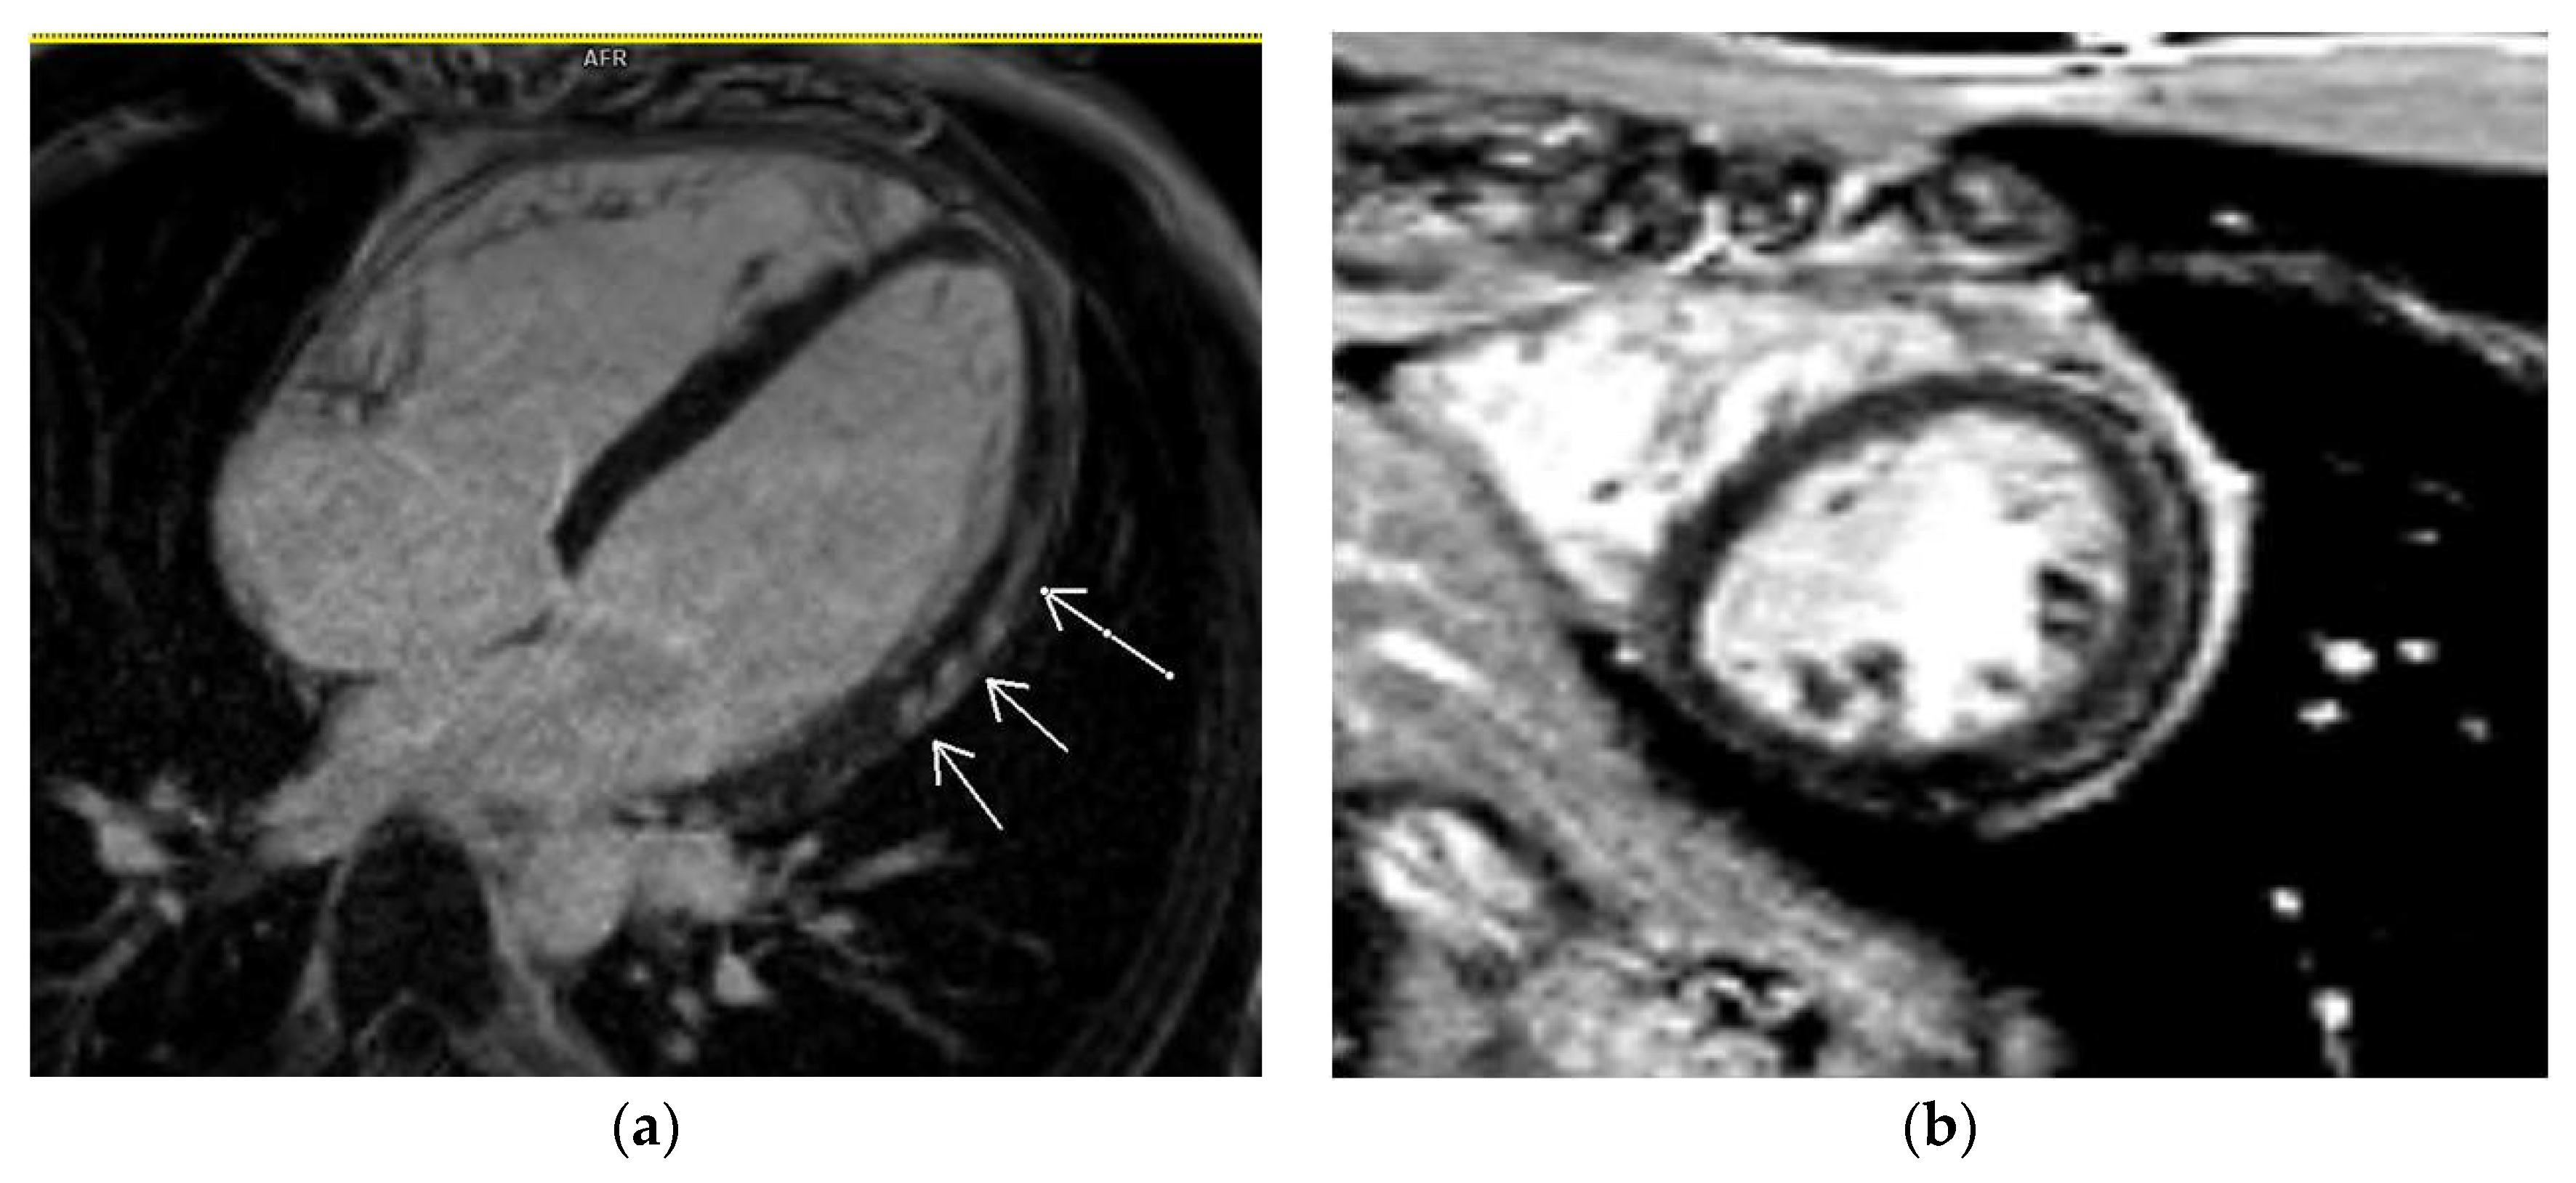

3.2. CMR Findings

3.5. LGE Localization